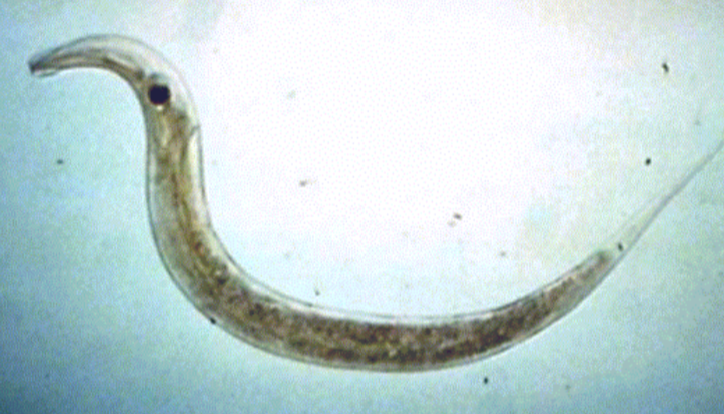

Stonglyloides stercoralis

Stonglyloides stercoralis